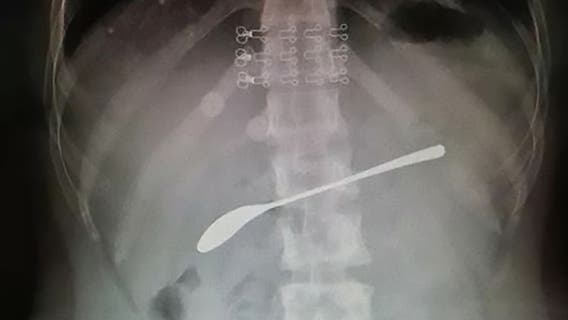

Drunk woman swallowed 6-inch spoon and forgot, report says

Doctors in China are making an example of a patient who allegedly got so drunk she swallowed a 6-inch spoon and forgot about it the next day.